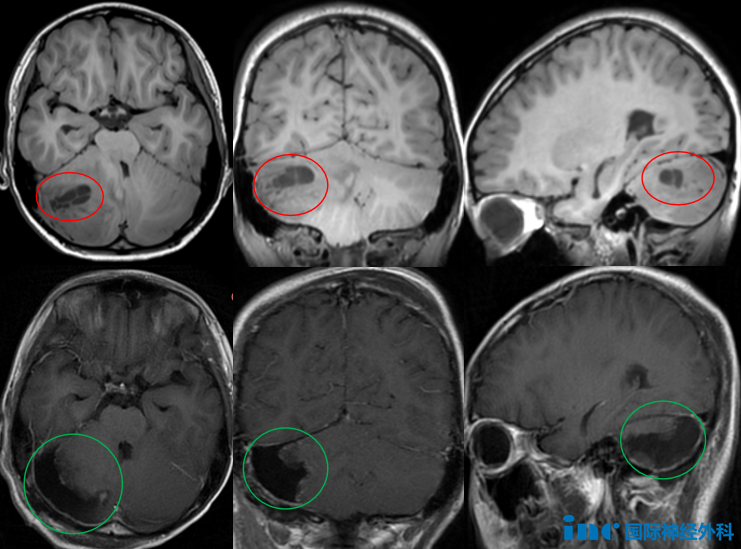

年仅9岁的九九,生命被一个巨大的恶性脑瘤按下暂停键。体积巨大、ki67高达60%-70%、位于小脑且严重压迫脑干、术前出现复视、剧烈头痛、精神萎靡……每一个特性似乎都预示了这位小男孩的命途多舛。

点击图片,让我们一起了解九九是如何从确诊为恶性脑瘤到决定找巴教授手术,最终实现全切、获得良好预后的。他的治疗之路也揭示了针对这种恶性脑瘤,治疗的重中之重是什么。

- 文章标题:恶性髓母细胞瘤治疗的重中之重,术后2年开心玩耍的他来告诉你!